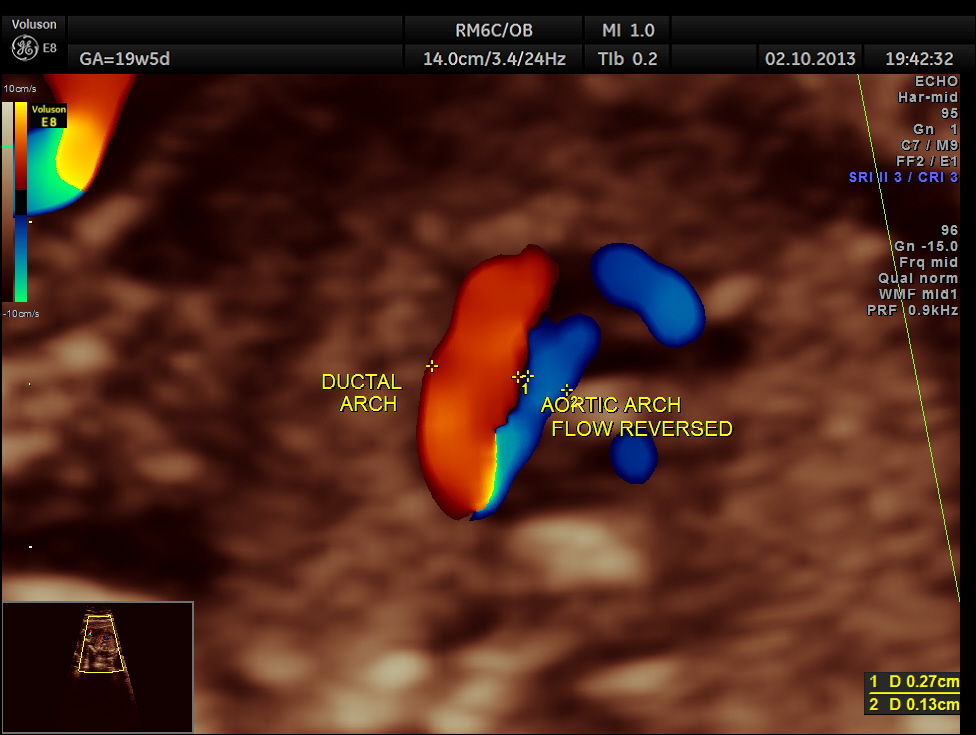

Aortic arch is progressively narrowed with the isthmus appearing very narrow. A flow reversal is also seen .

The following picture shows the reversal of flow in the foramen ovale , which according to some authors is a salient diagnostic feature of co-arctation of aorta.

The diagnosis offered was PROBABLE CO-ARCTATION OF AORTA .